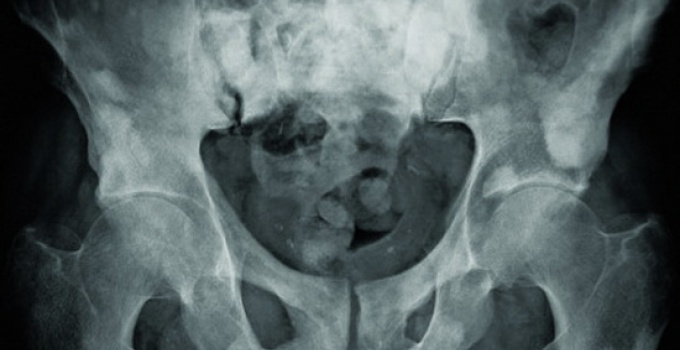

Bandelettes sous-urétrales : un risque de complication avéré, croissant avec les années

Incontinence urinaire : les bandelettes sous-urétrales en sursis ?

Vasectomie, bandelettes urinaires, kétamine... Que retenir du Congrès français d'urologie ?